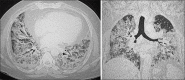

Results: The number of deceased males (82, 62.6%) was higher than females (53, 37.3%). Median age of deceased patient was 57 (44.25-69.75) years. Most frequent comorbidities were diabetes mellitus (42, 29.6%) and hypertension (41, 28.9%). Most common symptoms being shortness of breath (137, 96.5%), fever (94, 66.2%) and cough (73, 51.4%). Median peripheral capillary oxygen saturation (SpO2) at time of admission was 86% (77.25-90). Median time interval from symptom onset to admission in hospital was 3 (2.25-5) days. Neutrophil lymphocyte ratio was more than 5 in 117 (90.7%) patients. Complications seen were acute respiratory distress syndrome in 82.3%, acute liver injury in 58.4%, acute kidney injury in 26.7%, sepsis in 13.3% and acute cardiac injury in 12% patients. The median high-resolution computed tomography score was 20 (17-22).